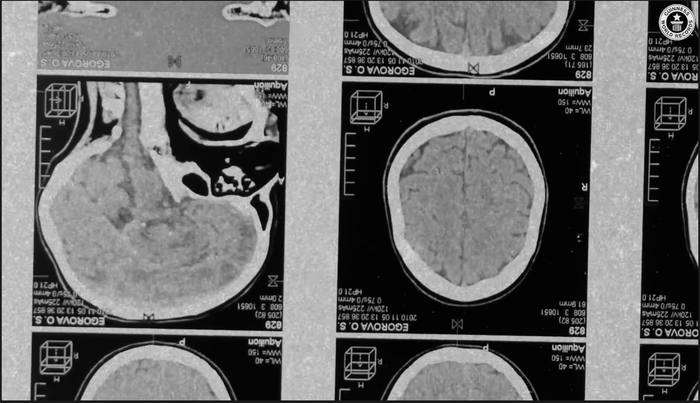

Подопытного звали Рэнди Гарднер, во время эксперимента он испытывал галлюцинации и ужасающие провалы в памяти. Сейчас такие опыты запрещены и даже уголовно наказуемы в большинстве стран — долгое отсутствие сна буквально разрушает мозг и вызывает сильнейшее воспаление.

Авторы обзора считают, что депривация сна подталкивает психику к тотальному состоянию психоза. Мозг человека, лишенного сна, перестает нормально координировать активность различных своих участков. В результате появляются пестрые симптомы в виде галлюцинаций, странных иллюзий (некоторые подопытные чувствовали, как их конечности растягиваются, становятся длиннее во много раз) и когнитивных нарушений.

Но самое страшное происходит позднее, когда нейроны, уже спятившие от нон-стоп режима, начинают разрушать сами себя. Этот последний этап воочию наблюдали только в опытах на животных, но, велика вероятность, Рэнди был близок к этому этапу.